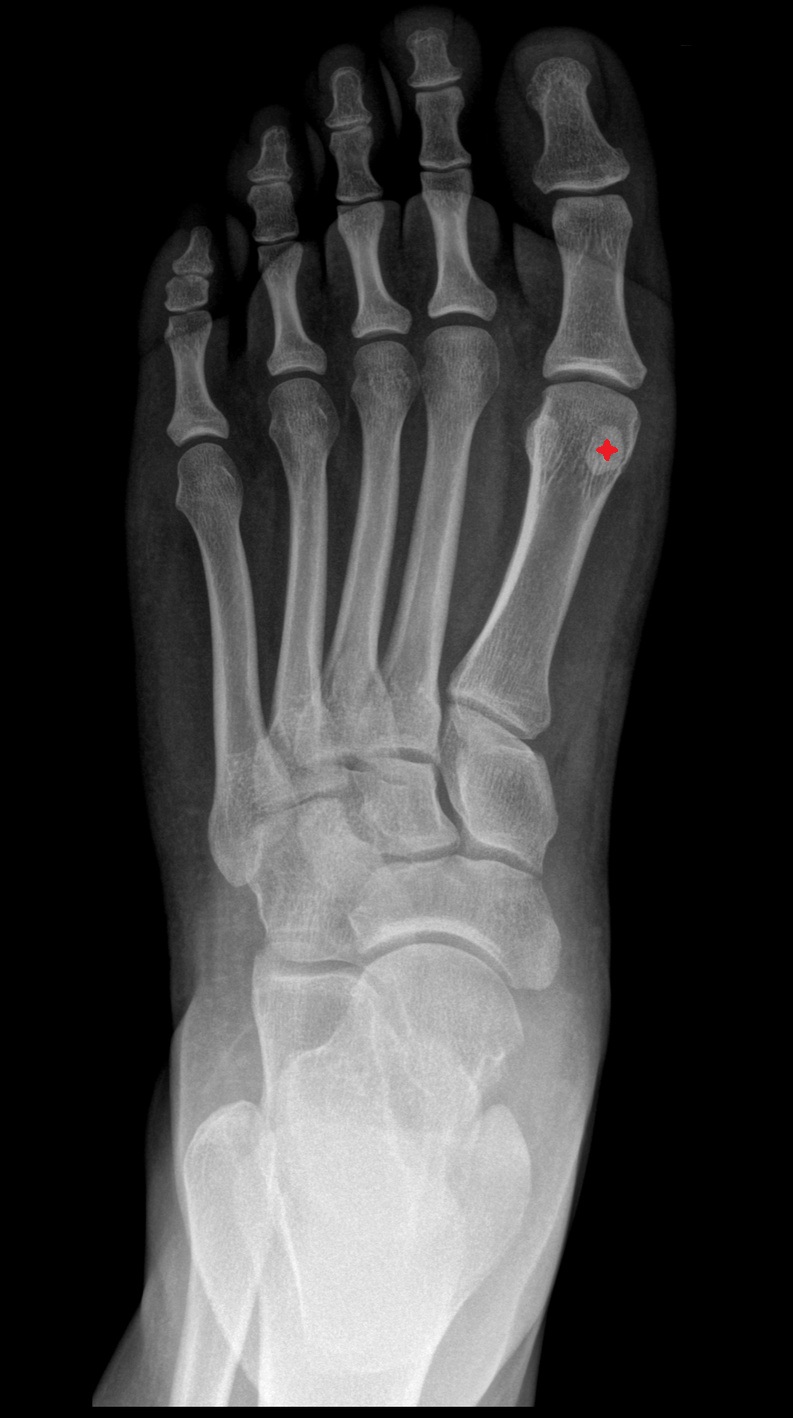

- First metatarsal bone

- Second metatarsal bone

- Third metatarsal bone

- Fourth metatarsal bone

- Fifth metatarsal bone

- Sesamoid bone of great toe

- Lateral sesamoid bone

- Medial sesamoid bone